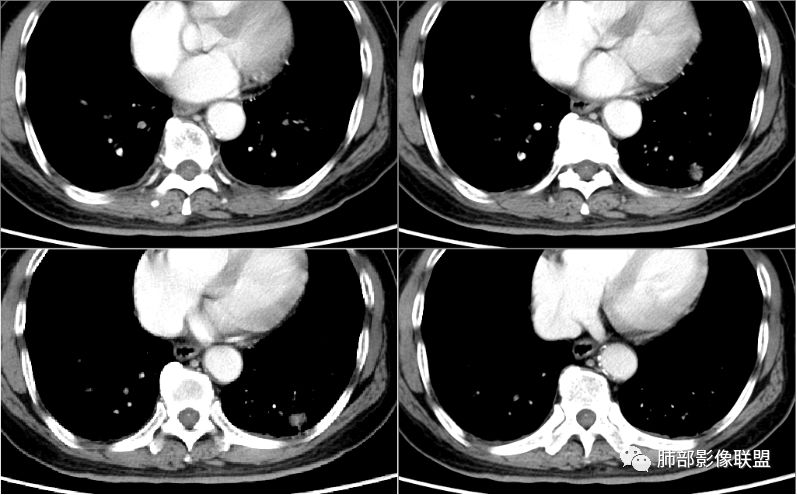

病例1为胸膜下实性小结节,血管脐凹样出入,可见支气管阻塞。病灶膨隆,部分边缘平直,周围晕征不明显,未见分叶,但可见毛刺及胸膜牵拉,增强后明显强化,老年男性,怀疑新生物尤其是腺癌是有理由的。

病例2肉瘤样癌的病理意见有些出乎预料,也充分说明病变及影像表现的复杂性。病灶小结节支气管截断、空泡、分叶、短毛刺、血管集束征等似乎均符合肺癌的影像特性。肺鳞癌及肉瘤样癌往往范围较小就可以出现坏死,但如果结节太小则很少能够在影像上观察到坏死区或空洞,没有增强扫描图像更是如此。

张立:第一例:增强后内可见血管,患者有神经系统症状,小细胞癌可能。

大雄:晨读一定要有个倾向的话第一个病例恶性,膨隆且强化明显,穿刺比较容易。